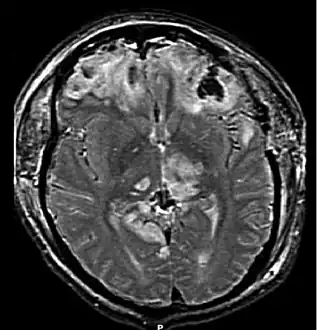

Magnetic resonance imaging (MRI) can show more detail than CT, and can add information about expected outcome in the long term.[32] It is more useful than CT for detecting injury characteristics such as diffuse axonal injury in the longer term.[27] However, MRI is not used in the emergency setting for reasons including its relative inefficacy in detecting bleeds and fractures, its lengthy acquisition of images, the inaccessibility of the patient in the machine, and its incompatibility with metal items used in emergency care.[32] A variant of MRI since 2012 is High definition fiber tracking (HDFT).[81]